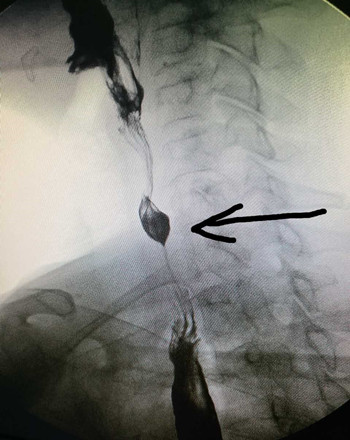

時隔1月,我科又于2017-03-06 17:00接診了第二例食管異物患者。該患者于6小時前進食時誤咽棗核,當時感咽部疼痛,無咳血及呼吸困難,無嗆咳,進食時疼痛加重。門診檢查食道造影示:第7頸椎平面可見異物。門診醫師遂以“食道異物”收住入院。入院后張立剛副主任醫師及劉教練主治醫師立即安排各項術前工作,急查上消化道鋇餐造影示:胸1椎體重疊處見梭形高密度影,結合食管造影,確定為食道異物。為防止患者出現食道感染及穿孔,遂急診在全身麻醉下行食道異物取出術。用硬質食道鏡直視下見食管入口下約2cm有一棗核,垂直扎入食管壁,有少許滲血,故異物鉗夾住棗核后慢慢退出,檢查食管壁無活動性出血后結束手術。從患者入院到手術結束,整個過程不到3小時。